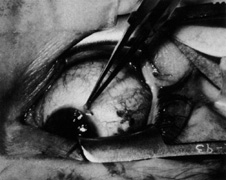

Step 1. The lateral rectus muscle is isolated through either a limbal (Fig. 1) or fornix incision. The muscle is dissected free of intermuscular septum and check ligaments for a distance of approximately 15 mm posterior to its insertion. When a fornix approach is used, the procedure can be performed through a single inferior temporal incision; however, making a second superior temporal fornix incision facilitates reattachment of the superior arm of the muscle.

Fig. 1. The lateral rectus muscle is isolated through a limbal incision and dissected free of intermuscular septum and check ligaments for a distance of approximately 15 mm posterior to its insertion.